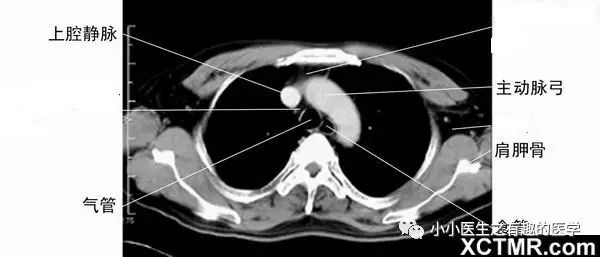

4.一定要知道主动脉弓。因为主动脉弓层面,是肺段划分的常用依据。到了主动脉弓,右肺分为前、尖、后段,左肺分为前、尖后段。这是看肺段的最基本入门知识。

另外,上腔静脉是很基本的血管,要知道。气管很重要,气管的后面,是食道。